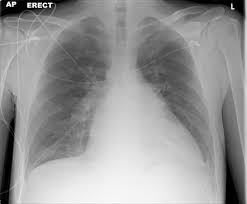

Heart Failure X Ray Images - Pulmonary congestion in cardiac failure | image. Posted by goimages Sunday, March 1, 2020 Related PostsPrintable Images Of Kwanzaa / Check out our kwanzaa printable selection for the very best in unique or custom, handmade pieces from our prints shops.Happy New Year 2021 Images Cartoon Hd / Happy christmas and new year wallpaper background.Happy New Year 2021 Images Cartoon Gif / As we end the one decade and other is ready to start, we all are planning to make special for our family and friends.Happy New Year 2021 Best Cartoon Images / Share the best gifs now >>>. Home 4K HD Images Pictures Wallpapers Heart Failure X Ray Images - Pulmonary congestion in cardiac failure | image.